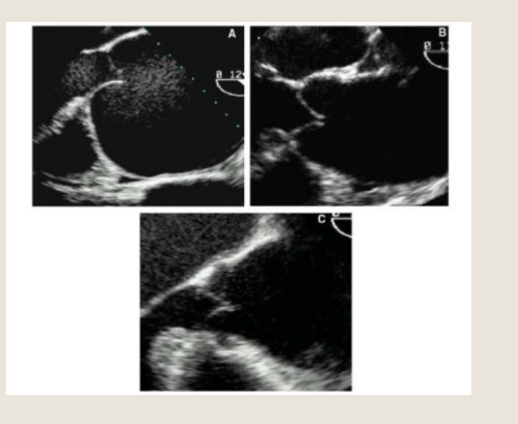

Aortic Valve Prolapse define and what is it highly associated with?

Aortic valve prolapse is a condition where the aortic valve's cusps move down

below the line that connects the valve leaflets to the annulus Highly associated with eccentric AR

VSD with Aortic Prolapse

Define in systole and what effect is this known as?

In early systole (left), blood ejected from the

left ventricle will be shunted through the

ventricular septal defect

The unsupported right coronary cusp and

right aortic sinus are driven into the right

ventricle. This limits left to right shunting of

VSD flow

This is known as the Venturi effect

in diastole

This is best evaluated in what view

In diastole (right), the intra-aortic pressure

forces the aortic valve leaflet to close, but

the unsupported right coronary cusp is

pushed down into the left ventricular

outflow tract away from the opposed

coronary cusp, resulting in regurgitation

This is best evaluated in PLAX